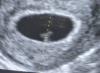

Последнее узи вот, 16 числа делала